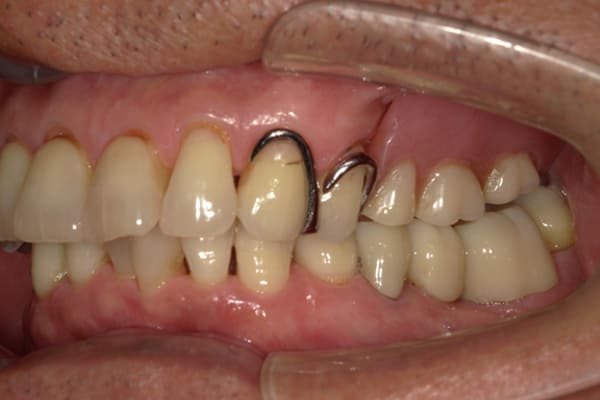

症例レポート[CASE.06]

- 男性(70代)

- 下歯がぐらぐらで抜けそうで痛い、何でも咬めるようにしてほしい

- 治療

- 上顎精密金属床部分入れ歯

- 下顎精密金属床部分入れ歯

- 陶材焼付鋳造冠 4歯

- 磁性アタッチメント 1歯

- 治療期間

-

- 上顎精密金属部分入れ歯:55万円

- 下顎精密金属部分入れ歯:77万円

(治療用義歯含、咬合平面等修正) - 陶材焼付鋳造冠:16.5万円×3歯

(ミリング加工) - 陶材焼付鋳造冠:14.3万円×1歯

(ミリングなし) - 磁性アタッチメント:11万円×1歯

(白金加金)

合計:157.3万円(税込)

奥歯がなくなり放置されていたため、前歯に負担がかかり、歯周病も併発されており歯がぐらぐらでお痛みも伴う状態でした。

可能な限り残せる歯は保存し虫歯治療を行い、どうしても残せないお痛みの歯のみ抜歯を行いました。

陶材焼着付鋳造冠 ミリングラべット加工

残りの歯が少ない場合は、入れ歯が動きやすく、またご自身の歯にも負担がかかるため、残りの歯の被せ物、入れ歯ともに、歯に負担がかかることを最小限にした特殊な加工を行い、歯を長持ちさせる設計としました。

上の入れ歯

下の入れ歯

上の入れ歯は、治療用入れ歯において、前方に違和感を訴えられていたため、違和感のない範囲を治療用入れ歯で決定し、最後の入れ歯に反映することで、上下ともに初めての入れ歯でしたが、違和感を感じることなくご使用になられることが可能になりました。

このように、お一人おひとり、お口の中の感覚は個人差が非常に大きいため、治療用の入れ歯でかみ合わせ、見た目、違和感、お痛みなど、あらゆる項目をチェックし、ご意見をお伺いし、ご相談のうえ最終的な入れ歯の設計を行い作製することで、その方に合った入れ歯が出来上がります。